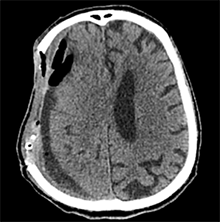

53 m. vyras sumuštas gatvėje ir greitosios medicinos pagalbos atvežtas į Priėmimo skyrių. Pacientui atlikta galvos kompiuterinė tomografija (GKT). Rasta: poūmė, stora, apie 16 mm dydžio subdurinė hematoma (SDH) dešinėje pusėje konveksitaliai ir ūmi nedidelė SDH kairėje pusėje frontoparietaliai. Vidurio struktūrų dislokacija (VSD) į kairę – minimali. Kairėje – kaukolės skliauto linijinis lūžis. Nustatyta nosies kaulų, nosies pertvaros, dešiniojo viršutinio žandikaulio kaktinės ataugos ir kūno, sinuso sienelių lūžių, dešinės akiduobės medialinio krašto lūžių ir dešiniojo skruostinio lanko lūžių (1 pav.). 2020 m. liepos mėn. pacientas skubos tvarka operuotas: atlikta dešinė kraniotomija, pašalinta hematoma. Atlikus kontrolinę GKT, buvo matyti, kad pašalinta didžioji hematomos dalis (2 pav.). Pacientas konsultuotas veido ir žandikaulio chirurgo, skubus chirurginis gydymas neindikuotas. Praėjus 3 savaitėms, pacientas, esant gerai funkcinei ir neurologinei būklei, tolesnio gydymo perkeltas į slaugos ligoninę, vėliau išleistas gydytis ambulatoriškai.

1 pav. Prieš pirmąją operaciją (poūmė, stambi, iki 16 mm SDH apie dešinįjį pusrutulį, ūmi nedidelė SDH kairėje F-P; VSD į kairę ~3 mm)